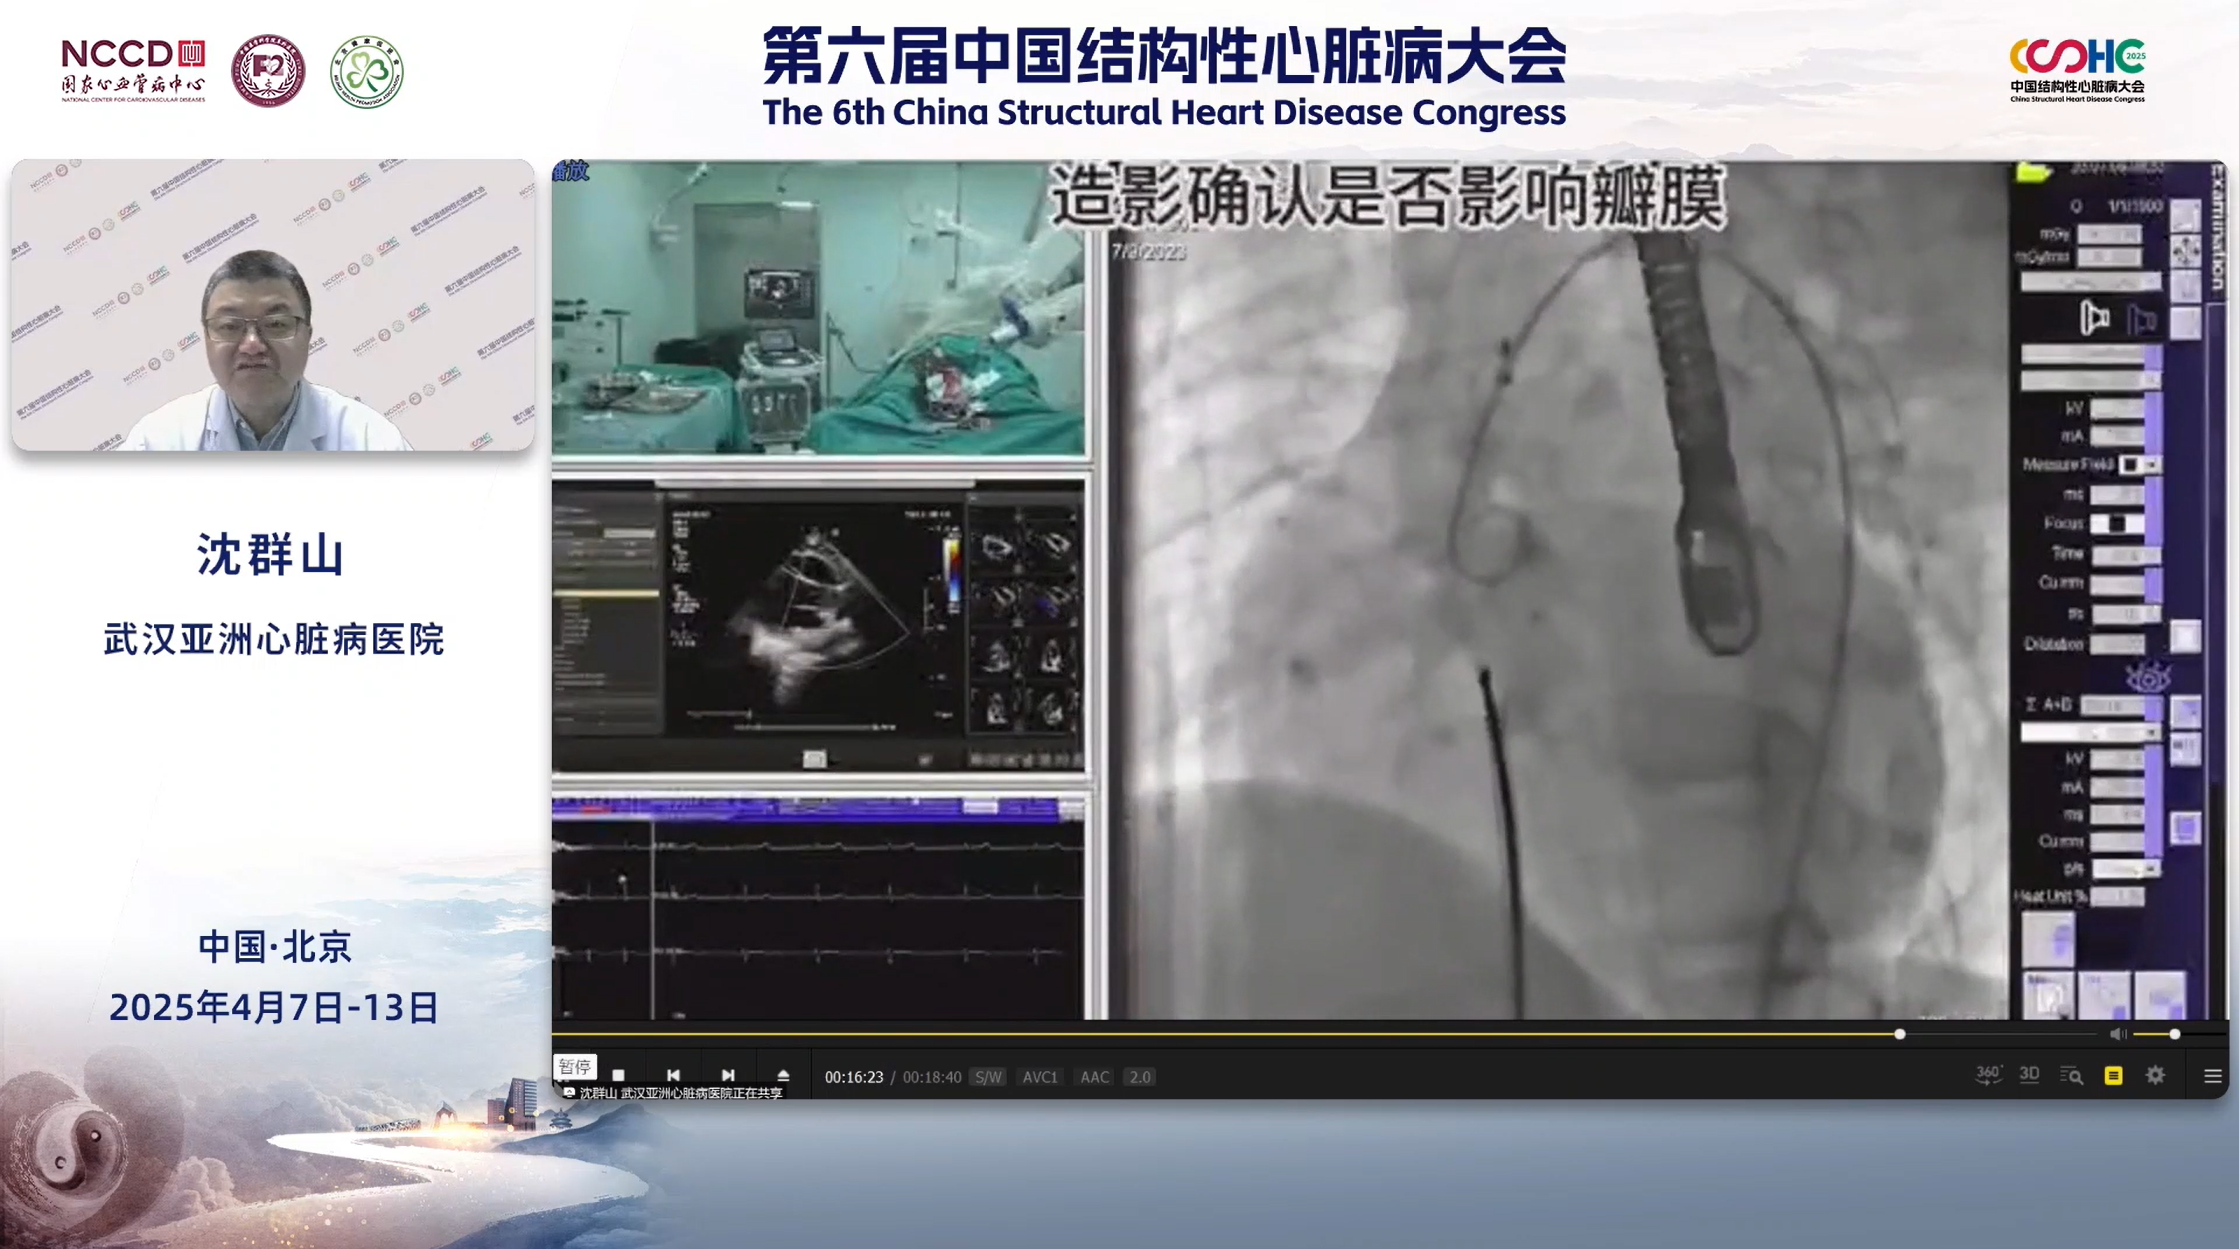

患儿14岁,超声诊断嵴下型室间隔缺损,缺损直径4 mm。该患者室间隔缺损位置较高,属于高位长管型室缺,靠近主动脉瓣,距离不足2 mm,术前超声提示存在轻度主动脉瓣反流。若采用金属封堵器,术后可能存在磨损瓣膜、影响主动脉血流的潜在风险,进而影响患儿的近远期预后。故决定选择ABFDQ-II 08全降解封堵器行VSD封堵。术中采用漂浮导丝的方法辅助建立动静脉轨道,以有效规避对传导系统的机械损伤,轨道建立后送入鞘管,再经鞘送入全降解封堵器。透视下,通过监测输送钢缆尾端和输送鞘前端的相对距离,可判断封堵器左盘面是否打开,联合超声引导,先释放左盘,稍用力牵拉确保其稳定贴附于室间隔后,回撤输送鞘,继续释放右盘。 经多切面超声反复验证后,牵拉成型线锁定。术后超声提示封堵器形态位置良好,呈标准工字型,未对主动脉及主动脉血流造成影响 ,且主动脉瓣反流较术前减轻,未见明显残余分流或血栓形成,心包腔内未见明显异常,手术效果理想,封堵成功完成。

锁定后牵拉测试

术后超声——封堵器形态呈标准工字型

沈群山教授(武汉亚洲心脏病医院):在处理靠近主动脉瓣的室间隔缺损时,若患者合并膜部瘤,可巧妙借助膜部边缘来选择合适封堵器。同时,精准测量室间隔缺损与主动脉根部的实际距离至关重要。而在封堵器释放环节,应尽可能使其贴合在无冠窦下方,以最大程度避免对主动脉瓣开合功能产生干扰。若在操作过程中因伞过早打开导致主动脉瓣卡压情况的出现,切勿强行释放,务必及时回收,即便此次操作未能成功,也绝不能对患者造成任何不必要的损伤。总体而言,对称性全降解室间隔封堵器在室间隔缺损介入治疗领域,展现出了极为出色的治疗安全性和有效性,尤其适合儿童及中青年患者的治疗期待,值得推广应用。